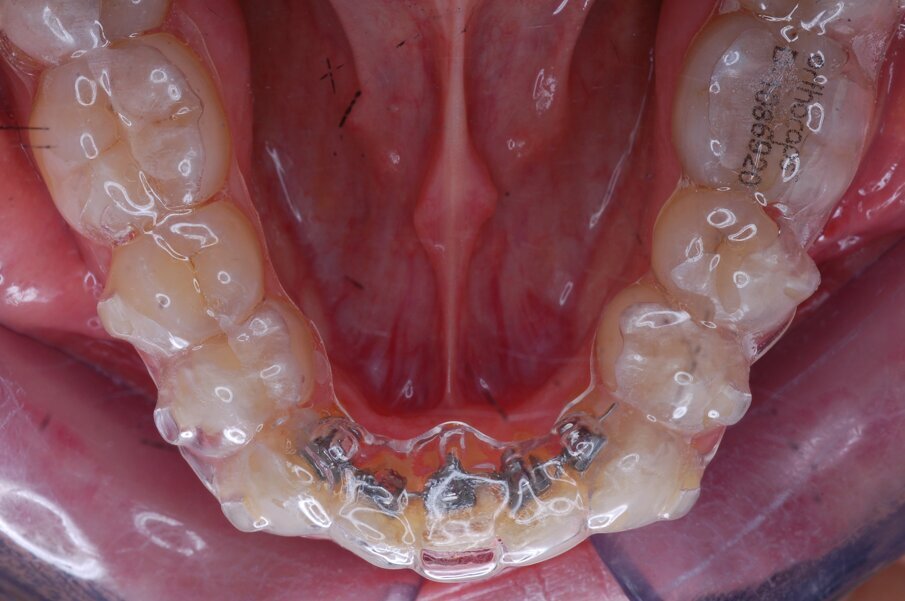

Diagnosi ed eziologia Un uomo sano di 39 anni si è presentato nel nostro studio ortodontico lamentando un aspetto dentale poco attraente e la paura della chirurgia ortognatica proposta da un altro ortodontista. Clinicamente, il profilo del paziente era rettilineo e la vista frontale non mostrava alcuna asimmetria facciale. L’esame funzionale non ha rivelato alcuna deviazione mandibolare o riduzione dei movimenti. Il paziente non aveva dolori articolari e non sono stati rilevati rumori articolari. Era presente una lieve occlusione molare bilaterale di Classe II, un morso aperto e un grave affollamento in entrambe le arcate. L’affollamento era particolarmente grave nell’arcata mandibolare, sebbene mancasse l’incisivo centrale mandibolare destro. Gli incisivi mascellari erano di piccole dimensioni, suggerendo una discrepanza dell’indice di Bolton se fossero stati presenti tutti e quattro gli incisivi mandibolari. Erano inoltre presenti un morso incrociato nella regione dell’incisivo laterale superiore sinistro e una grave rotazione distale del secondo premolare mandibolare sinistro (Figg. 1-8).

Figg. 1-8_Fotografie facciali e intraorali pre-trattamento.

Figg. 25-29_Progressi clinici dopo 12 mesi di trattamento con allineatori.